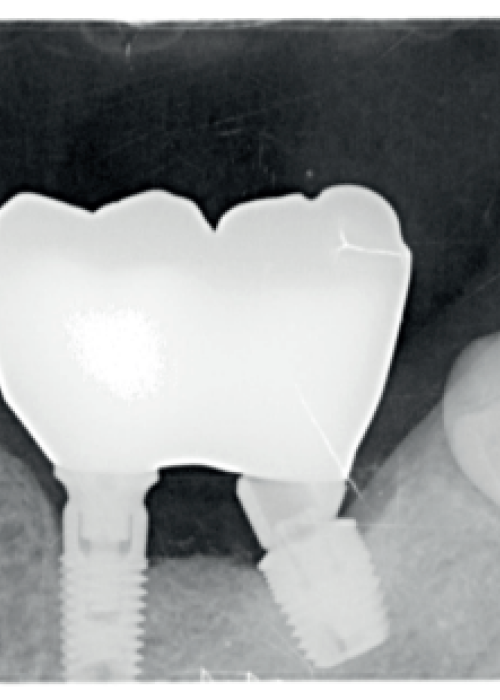

Utilización de dentina autóloga como material de regeneración. Rehabilitación de un paciente mediante tratamiento quirúrgico y prostodóncico con flujo digital